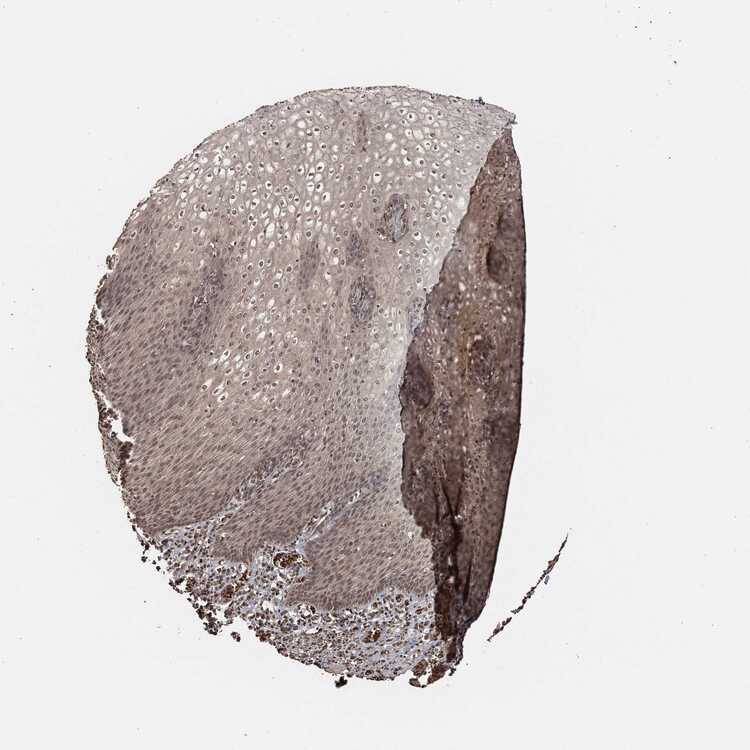

TISSUE PRIMARY DATA ESOPHAGUS Show tissue menu

ESOPHAGUS - Antibody stainingi

Antibody staining in the annotated cell types in the current human tissue is reported as not detected, low, medium, or high, based on conventional immunohistochemistry profiling in selected tissues. This score is based on the combination of the staining intensity and fraction of stained cells.

Each image is clickable and will lead to virtual microscopy that enables deeper exploration of all samples and also displays staining intensity scores, fraction scores and subcellular localization as well as patient and tissue information for each sample.

Antibody HPA001200Antibody HPA018530Antibody CAB000035Antibody CAB068186Antibody CAB073534Antibody CAB080313Antibody CAB080314Antibody CAB080473Antibody CAB080475Antibody CAB080506Antibody CAB080507Antibody CAB080509Antibody CAB080510Antibody CAB080511

Squamous epithelial cells Not detectedHighMediumNot detectedMediumHighHighMediumHighMediumHighNot detectedNot detectedNot detected